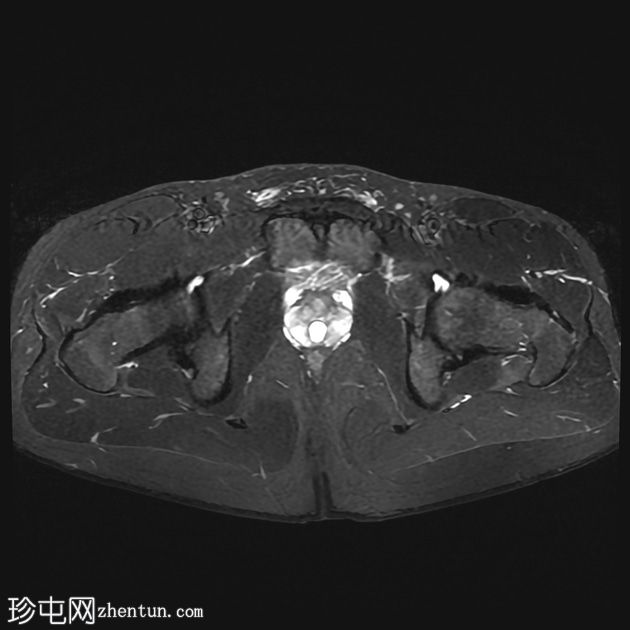

轴位

STIR序列

前列腺大小为32.8 x 41.5 x 34.7 mm(前后径 x 宽度 x 头尾径),体积为25.88 ml,属于正常范围。前列腺中央可见一逗号状囊性占位性病变,大小为17.3 x 12.1 x 9.3 mm(头尾径 x 前后径 x 宽度)。可见囊肿与前列腺尿道相通。囊内未见可疑内容物——具体而言,未见囊内出血或碎屑——弥散加权成像结果为阴性,提示无囊内感染。

动态增强扫描显示前列腺呈均匀强化,未见可疑的周边部或移行区异常。精囊正常。膀胱正常。盆腔内未见可疑淋巴结。

本例为一例发生于青年人的单纯性逗号状中央型前列腺内囊肿。

根据囊肿位于前列腺中央或中线(精阜水平)、患者年龄(二十岁左右)以及无前列腺外延伸和明显的尿道交通,前列腺囊肿是首选诊断。苗勒氏管囊肿通常难以排除。患者的年龄、无前列腺外延伸以及疑似尿道交通使该诊断的可能性降低。